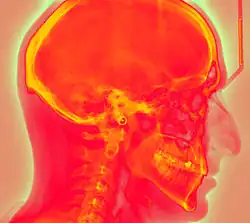

Projectional radiography using a photostimulable phosphor plate as an X-ray detector can be called "phosphor plate radiography"[1] or "computed radiography"[2] (not to be confused with computed tomography which uses computer processing to convert multiple projectional radiographies to a 3D image).

Computed radiography is used for both industrial radiography and medical projectional radiography. Image plate detectors have also been used in numerous crystallography studies.[5]

Medical X-ray Imaging

In phosphor plate radiography, the imaging plate is housed in a special cassette and placed under the body part or object to be examined and the x-ray exposure is made. The imaging plate is then run through a special laser scanner, or CR reader, that reads and converts the image to a digital radiograph. The digital image can then be viewed and enhanced using software that has functions very similar to other conventional digital image-processing software, such as contrast, brightness, filtration and zoom. CR imaging plates (IPs) can be retrofitted to existing exam rooms and used in multiple x-ray sites since IPs are processed through a CR reader (scanner) that can be shared between multiple exam rooms.[6]